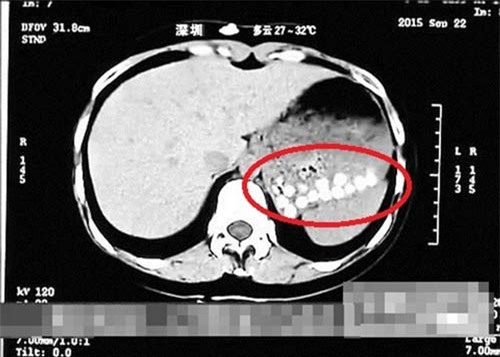

Tháng 10/2015, một đoạn phóng sự của Đài Truyền hình Sơn Đông, Trung Quốc tiết lộ sự thật về thành phần làm ra những viên trân châu dẻo dai ngon lành là từ... đế giày da và lốp xe cũ. Một phóng viên của đài thậm chí còn uống thử trà sữa trân châu, sau đó chụp CT sau 40 phút và kết quả ảnh chụp cho thấy dạ dày của phóng viên xuất hiện những chấm nhỏ li ti mãi không tan.